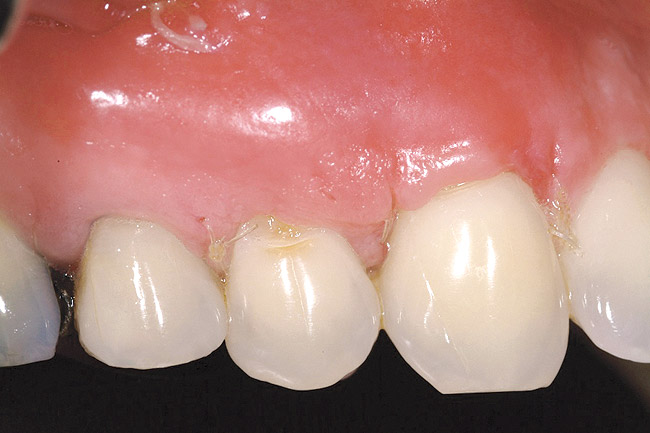

Figure 16  Case Two Preoperative clinical view, maxillary left central incisor.

Figure 16

A 27-year-old non-smoking man presented for esthetic enhancement of the left central incisor, which had a pre-existing full-coverage restoration that required replacement (Figure 16). The patient had begun orthodontic treatment in the mandibular arch to correct a minor occlusal imbalance and required coronal repositioning and soft tissue grafting to correct gingival recession at the facial of the right canine, in addition to correction of the free gingival margin at the facial of the left central incisor, which was asymmetrical to the free gingival margin of tooth No. 8. Additionally, the facial gingival tissues were of a thin biotype, which at the facial surface of the left central incisor allowed for the darkened root surface to be visible through the tissue (Figure 16).

The treatment plan was to accomplish an increased zone of keratinized tissue at tooth No. 6, and increase the thickness of the facial tissue at tooth No. 9, in addition to coronally repositioning the free gingival margin. Complicating this treatment plan was the fact that at the facial surface of tooth No. 9, a biologic width invasion was present due to the prepared margin for the pre-existing restoration being placed too close to the facial alveolar crest of bone (the patient had presented to the periodontist with a provisional restoration in place). Any correction to the area would require movement of the facial margin of the tooth in a coronal fashion to re-establish the appropriate distance from the facial height of bone to the margin of the restoration. Additionally, options were given to the patient for harvesting the soft tissue, using connective tissue from the palate, or the use of an acellular dermal matrix graft, which would nullify harvesting tissue from the palate region.